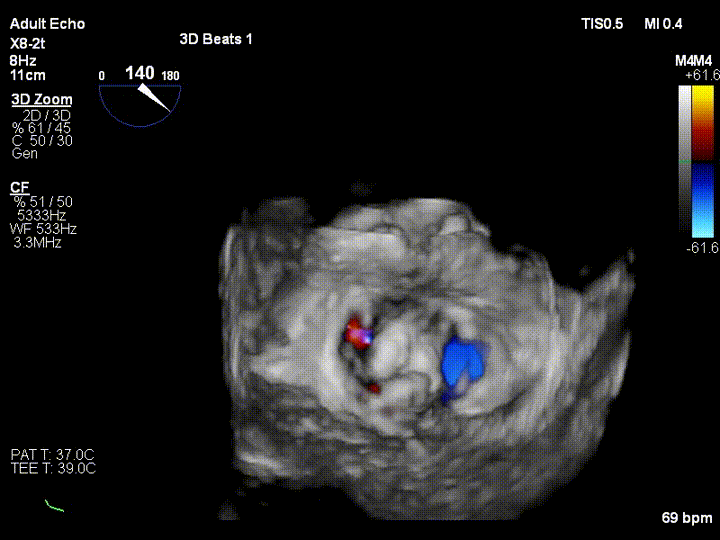

该患者是一名71岁老人,反复气喘3年余,加重3周余。入院诊断为二尖瓣后叶脱垂伴重度关闭不全,超声心动图提示:二尖瓣后叶脱垂伴重度关闭不全。该患者同时合并冠心病、房颤、外周动脉硬化、肾功能不全等疾病,心脏团队评估患者开胸手术风险极高,微创二尖瓣修复手术是最适合的治疗方式,因此患者及家属充分考虑后选择该项技术治疗,并签署本研究知情同意书,王焱教授团队全面评估后确认该患者符合本研究入选标准,注册入选成为福建省第一个入组治疗的患者。

王焱教授团队和美国弗吉尼亚大学医学中心David Scott Lim教授、香港亚心医院林逸贤教授术前详细评估并制定了相应的手术策略,并在手术当天在线指导。在浙江大学附属第二医院王建安书记结构团队核心成员刘先宝主任的现场指导下,王焱院长团队顺利完成股静脉穿刺,然后在食道超声指引下顺利穿刺理想位置的房间隔,肝素化后,放置25F鞘管至左房,测定左房压,随后顺利于二尖瓣前后叶植入两枚二尖瓣钳夹装置,术前患者二尖瓣重度反流即刻减轻至微量,左房压力即刻减低,预示着患者的临床症状将得到明显改善。手术全程用时不到2小时,患者术后即刻拔管苏醒。